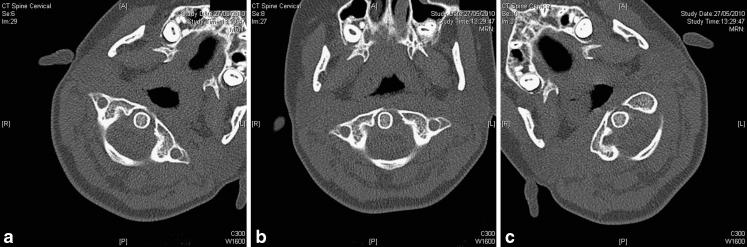

脊柱CT成像的技术层面

Technical aspects of CT imaging of the spine.

This review article discusses technical aspects of computed tomography (CT) imaging of the spine. Patient positioning, and its influence on image quality and movement artefact, is discussed. Particular emphasis is placed on the choice of scan parameters and their relation to image quality and radiation burden to the patient. Strategies to reduce radiation burden and artefact from metal implants are outlined. Data acquisition, processing, image display and steps to reduce artefact are reviewed. CT imaging of the spine is put into context with other imaging modalities for specific clinical indications or problems. This review aims to review underlying principles for image acquisition and to provide a rough guide for clinical problems without being prescriptive. Individual practice will always vary and reflect differences in local experience, technical provisions and clinical requirements.

这篇综述文章讨论了脊柱计算机断层扫描(CT)成像的技术方面。探讨了患者体位及其对图像质量和运动伪影的影响。特别强调了扫描参数的选择及其与图像质量和患者辐射负担的关系。概述了减少金属植入物辐射负担和伪影的策略。回顾了数据采集、处理、图像显示以及减少伪影的步骤。针对特定临床指征或问题,将脊柱CT成像与其他成像方式进行了对比。本综述旨在回顾图像采集的基本原则,并为临床问题提供一个大致的指导,而非给出具体的规定。个人实践总会有所不同,反映出当地经验、技术条件和临床需求的差异。